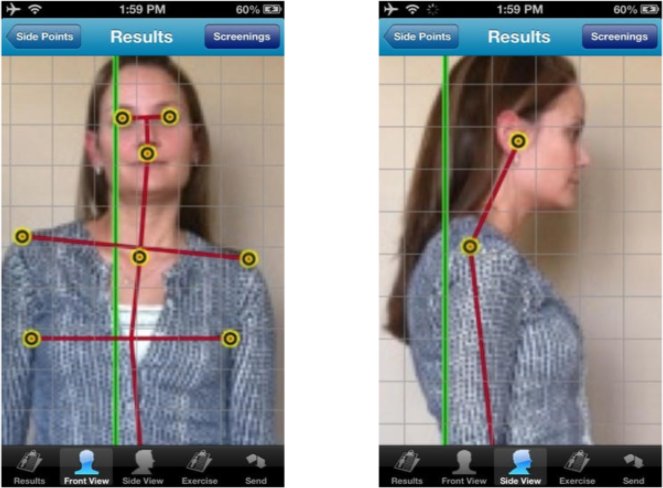

Posture Measurement Applications

A picture is worth a thousand words. So take a picture of your patient from the side and front and show them how their posture is off. This can be done using an app that is designed to do this. Or if you prefer, just have your patient stand in front of a posture grid or plumb line and take their picture. The point is to be able to show them how their posture is not normal. This is a great way to demonstrate the need for care. But it’s also a great visual aid in demonstrating the improvements in posture.

One thing I always did was take pictures of patient posture using THEIR phone as well. We all know how everyone likes to show their friends what their doctor said. Give them the pics and I promise they’ll end up showing them to their friends who will also want to come to you and get the same tests done. I’ve witnessed this time and time again.